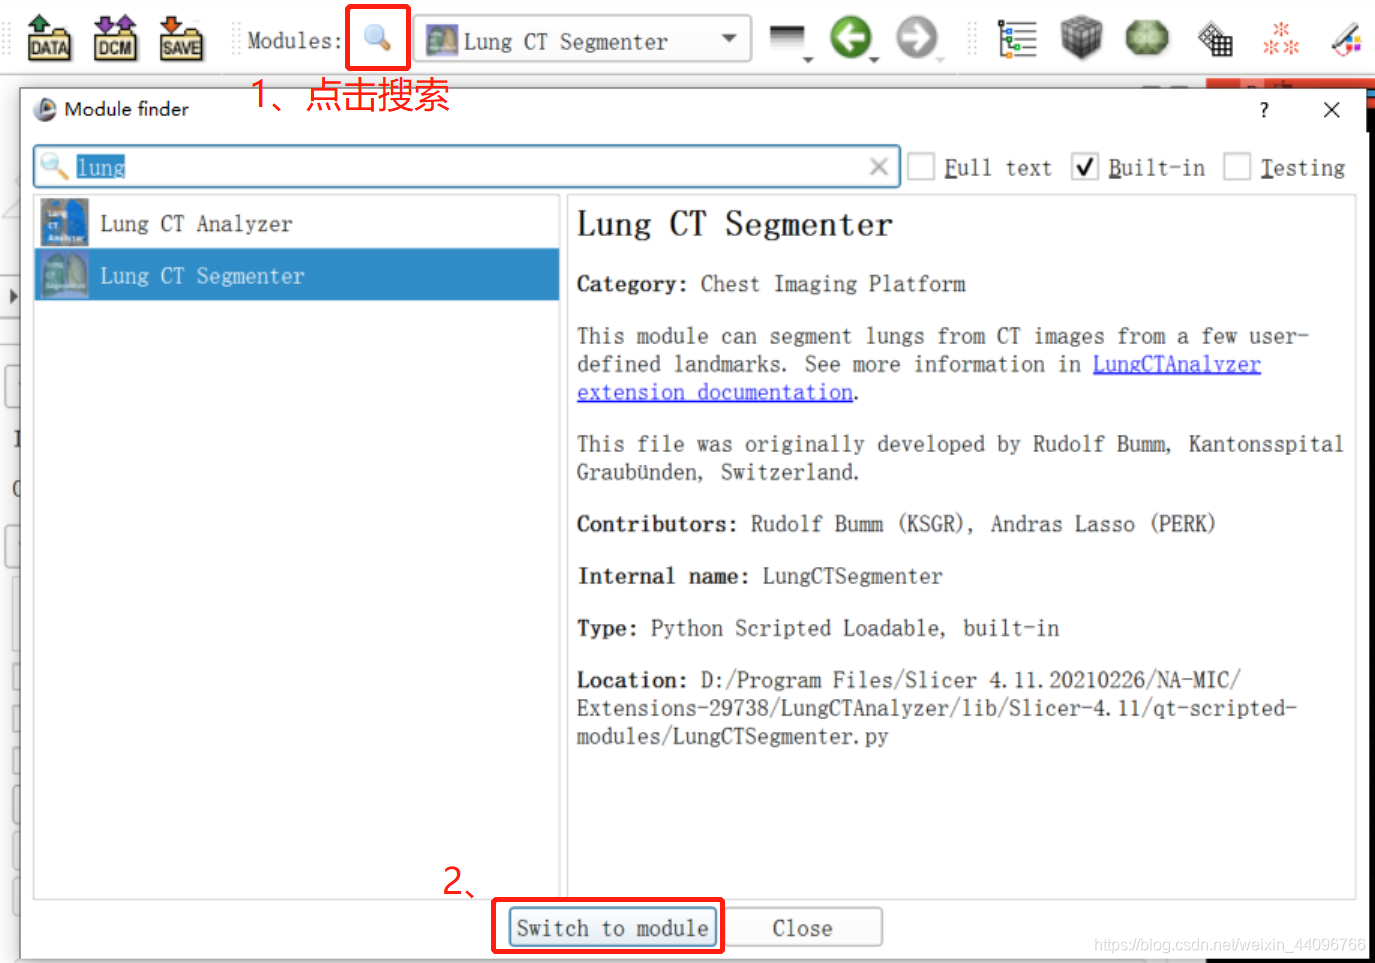

肺部分割

- 进入插件